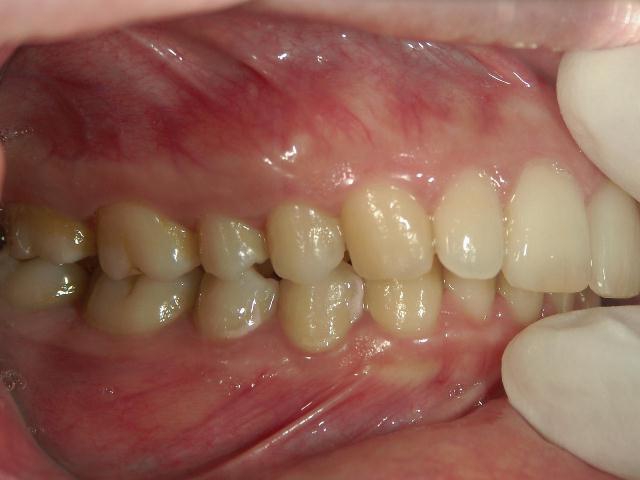

矯正歯科 治療前 右

矯正歯科 治療後 右